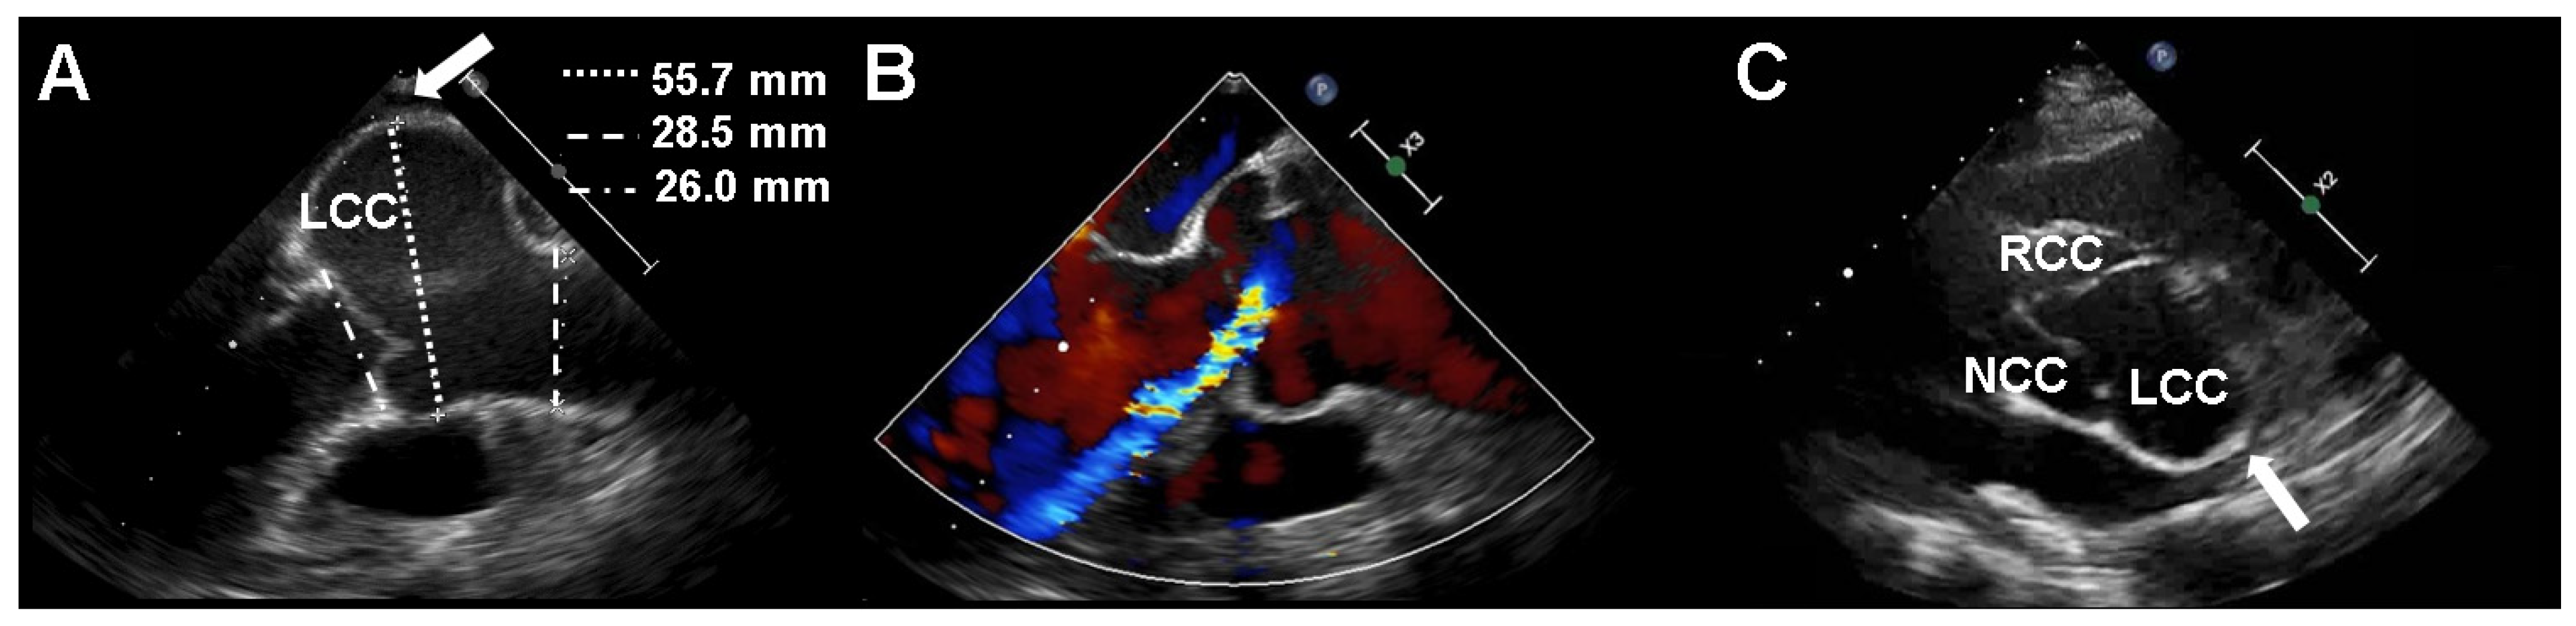

2. Case Presentation